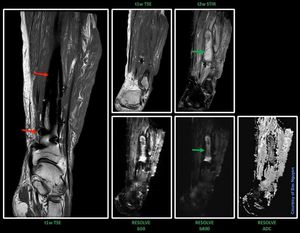

Intramedullary rod in the tibia along with some screws (red arrows)

Surprised a coronal RESOLVE DWI could be pulled off, showing abscess (green arrow).